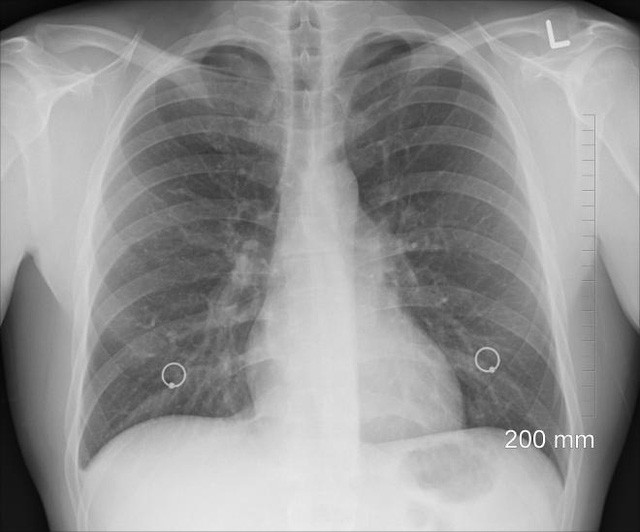

Một phổi

Nếu cơ thể chúng ta có hai thứ gì đó, thì không hẳn là chúng ta cần cả hai. Việc sống chỉ với một phổi, hoặc có thể là một phổi rưỡi, không khác gì nhiều với việc có cả hai phổi. Người ta có thể nghĩ rằng mất đi một lá phổi sẽ làm giảm một nửa khả năng hô hấp, nhưng không phải vậy vì cơ thể con người có dự trữ đáng kể.

Người đã phẫu thuật cắt bỏ một bên phổi vẫn giữ được từ 70 đến 80% chức năng hô hấp. Phổi còn lại sẽ sớm giãn nở bù cho bên phổi bị mất, và tập thể dục đều đặn sẽ đẩy nhanh này. Hoạt động gắng sức có thể khó khăn hơn, nhưng tập thể dục bình thường không bị ảnh hưởng nếu một bên phổi bị cắt bỏ.

Một tác dụng phụ chính là di lệch, vì phổi mất đi để lại khoảng trống. Lồng ngực sẽ xẹp nhẹ; tim, gan và phổi còn lại sẽ dồn về chỗ trống; và dịch sẽ lấp đầy phần còn lại của khoang. Cuối cùng, dịch sẽ bị keo hóa thành đám dính phổi.

Hệ quả của tất cả hoạt động này là cột sống có thể cong 15 – 30 độ về phía bên phổi bị mất, thường dễ nhận thấy nếu nhìn từ đằng sau khi đứng thẳng. Trong một số trường hợp, sự di lệch này có thể gây cản trở hô hấp.